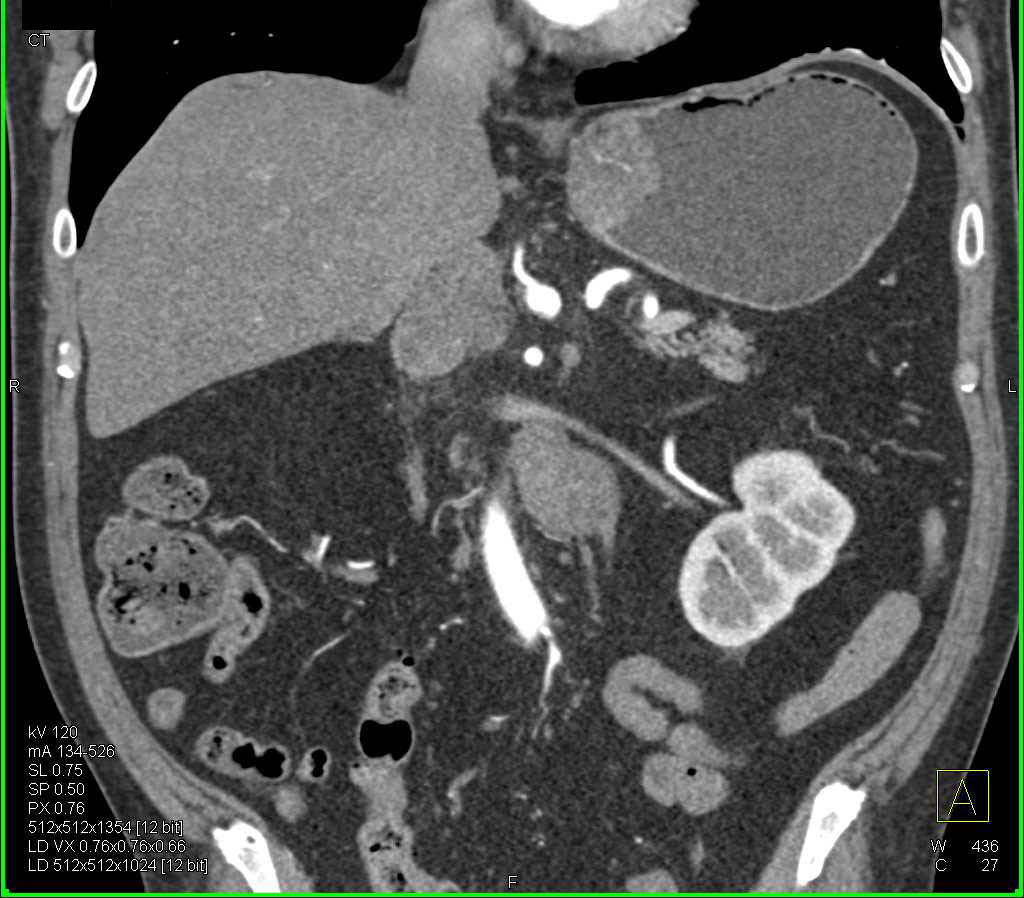

Stomach cancer CT – wikidoc

Gastric Cancer with Extensive Adenopathy – Stomach Case Studies …

Gastric Cancer with Extensive Adenopathy – Stomach Case Studies …

Gastric Cancer with Adenopathy – Stomach Case Studies – CTisus CT Scanning

Imaging Findings of Gastric Carcinoma | IntechOpen

Stomach Cancer On Ct Scan

Gastric Carcinoma | Radiology Key